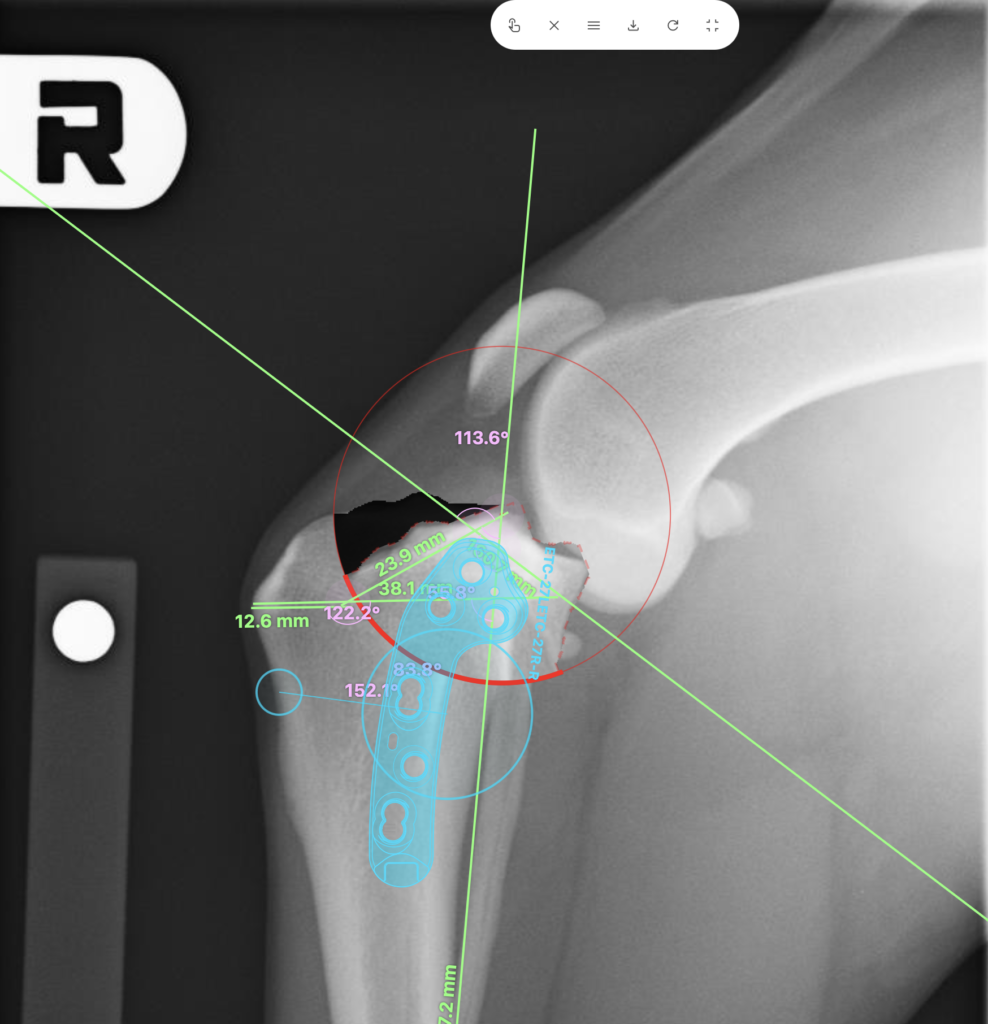

TPLO(脛骨高平部水平化骨切り術)

脛骨の形を外科的に変えることで、靭帯がなくても膝が安定するようにする術式です。

特に大型犬や活動的な犬において、長期的な予後が良好であるとのコンセンサスが得られています。